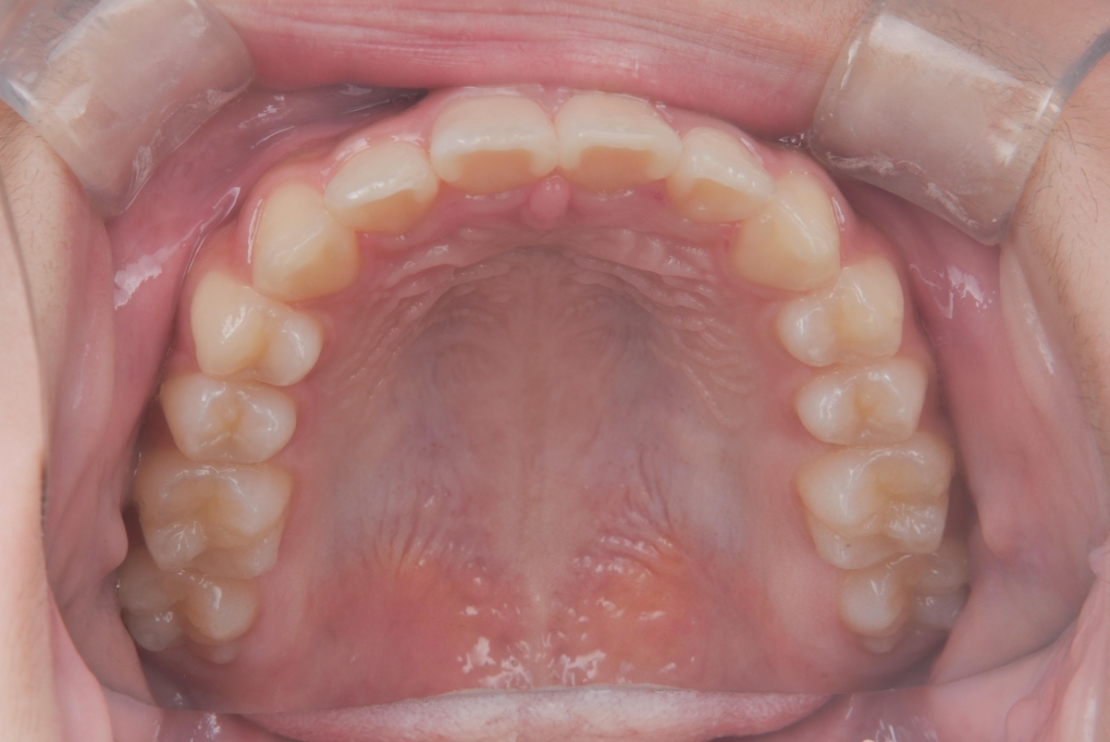

AFTER

治療期間は合計2年9ヶ月で、上下前歯のガタつきは改善し、見た目と機能の両面が整った歯列へと改善しました。

| 施術内容 | プレオルソ+歯全体のマウスピース矯正システム「インビザラインファースト」を用いた治療 |

| 治療期間 | 2年9ヶ月 |